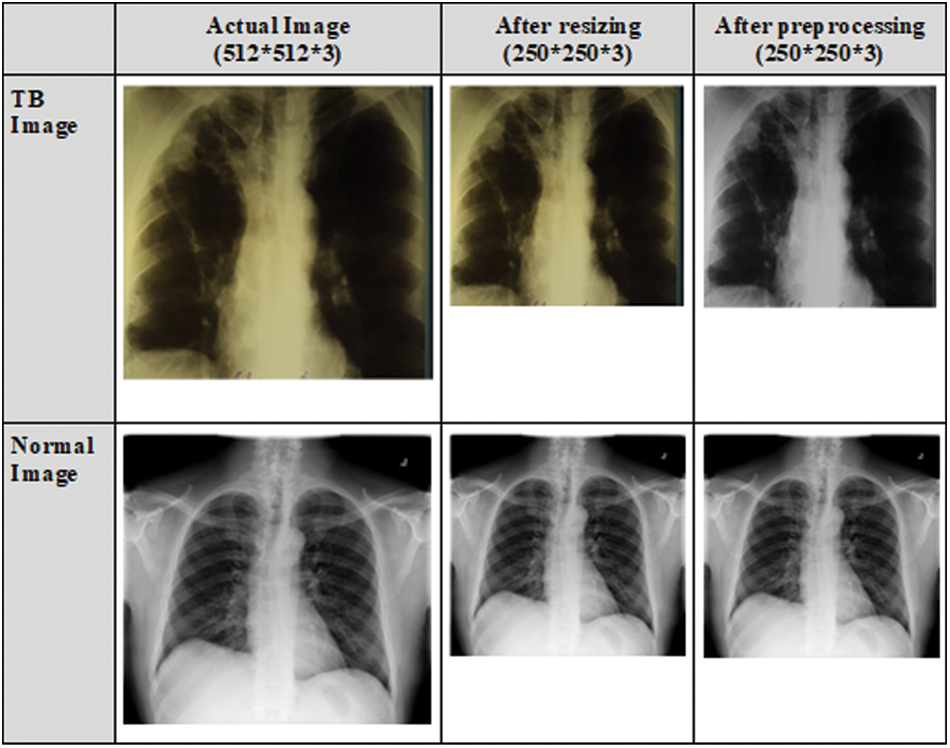

The CXR images in the dataset vary in size, and the majority of the CXR images contain one color channel (grayscale), but a few images have three color channels (RGB). Initially, all CXR images are converted to RGB images. To remove the effect of the blue color, RGB images are converted to grayscale images. The datasets are pre-processed to resize the CXR images as the size of the input images for various CNN models vary. Portable Network Graphics (PNG) format is used to resize the CXR images to 250 × 250 × 3 pixels. This size was chosen to meet the requirements of the input shape. Fig. 3 depicts the normal and TB images after resizing and pre-processing.

Figure 3: CXR images after resizing and pre-processing